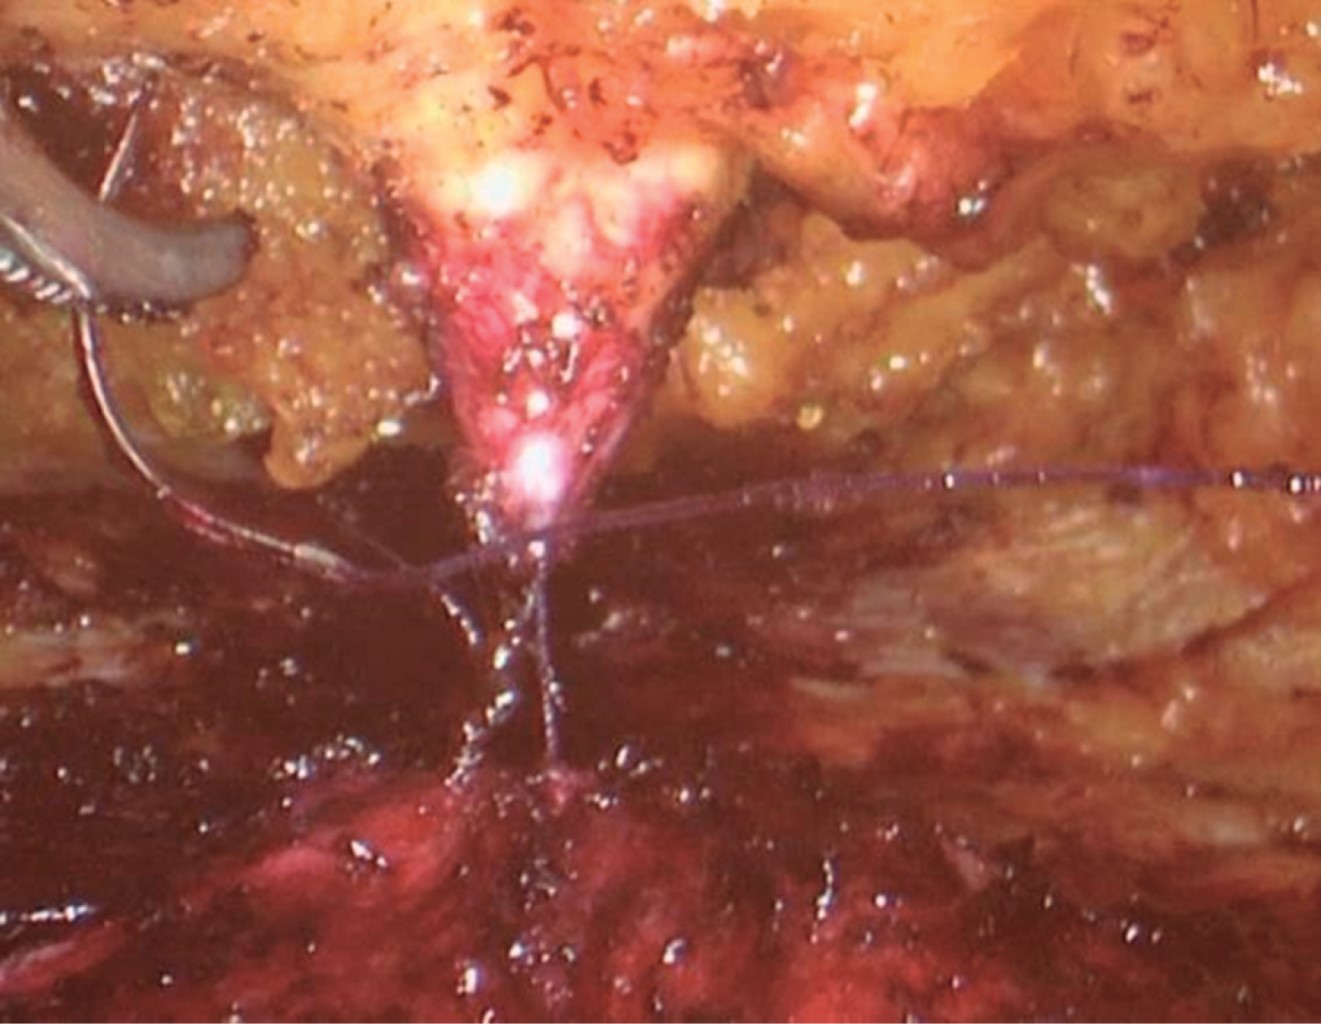

Under general anesthesia, the patient is placed in dorsal decubitus in the extended lithotomy position. The limits of the extent of the dissection are marked (Figure 1). A transverse incision is made 1.5 to 2 cm above the pubis. Then, the subcutaneous tissue is dissected up to the anterior aponeurosis of the rectus abdominis; using digital dissection, the subcutaneous cellular tissue is separated from the aponeurosis superiorly and laterally to create an ideal space for the placement of an 11 mm port for the optics through the suprapubic incision and two 5 mm working ports in both lower quadrants (Figure 2). CO insufflation pressure2 is maintained at 8-10 mmHg. Using harmonic scissors, subcutaneous dissection is performed from the suprapubic incision. The umbilicus is disinserted from the aponeurosis, and the dissection continued up to the xiphoid process and laterally to the semilunar line (Figure 3). The defects are quickly identified, the hernial sac is dissected, and the contents are reduced to the abdominal cavity (Figure 4). Once the dissection is completed, the diastasis of the rectus abdominis muscles is easily identified (Figure 5). The mesh continues to be made according to the size of the defects and considers the principles of hernia repair. The mesh is then placed in the preperitoneal space, and the defect is closed with a non-absorbable suture (Figure 4). The marking of the diastasis is continued, and the plication proceeds, which should extend from the xiphoid process to 2-3 cm below the umbilicus. In this case, barbed sutures were used and are recommended to facilitate plication without losing traction (Figure 5). The umbilicus is reattached to the muscular aponeurotic plane with one or two simple sutures (Figure 6). An aspiration drain is introduced to prevent seroma formation and is externalized through a 5 mm incision (Figure 7).

Figure 4

Figure 5